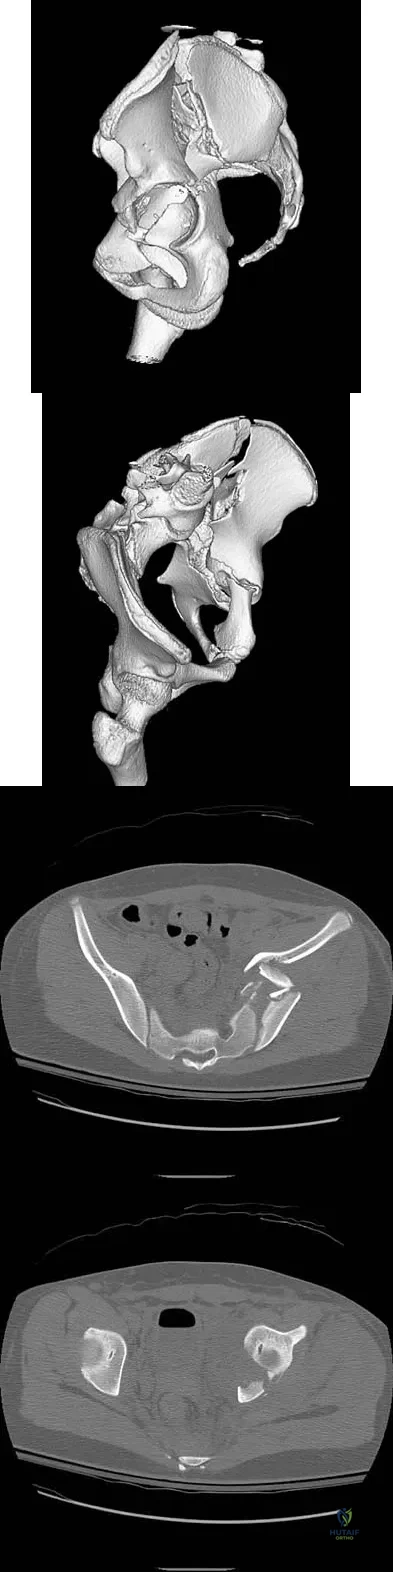

A 13-year-old girl was riding on an all-terrain vehicle when the driver struck a tree. She sustained the injury shown in Figures 45a through 45d. This injury is best described as what type of acetabular fracture pattern?

Correct Answer: Both-column

The fracture is a both-column fracture in the Judet/Letournel classification and a C3 in the AO classification. There is extension into the sacroiliac joint along the pelvic brim and comminution along the posterior column above the sciatic notch. Both the anterior and posterior columns are separately broken and displaced. However, the defining feature of a both-column pattern, as seen in this patient, is that all articular fragments are on fracture fragments and no joint surface is left intact to the axial skeleton above. The use of three-dimensional images makes it easier to view the location of the fracture fragments and the amount and direction of displacement. Helfet DL, Beck M, Gautier E, et al: Surgical techniques for acetabular fractures, in Tile M, Helfet DL, Kellam JF (eds): Fractures of the Pelvis and Acetabulum. Philadelphia, PA, Lippincott Williams & Wilkins, 2003, pp 533-603. Tile M: Describing the injury: Classification of acetabular fractures, in Tile M, Helfet DL, Kellam JF (eds): Fractures of the Pelvis and Acetabulum, ed 3. Philadelphia, PA, Lippincott Williams & Wilkins, 2003, pp 427-475.